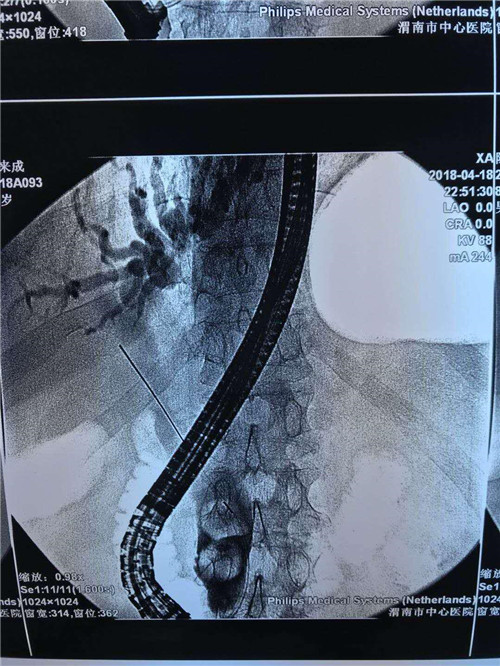

该患者男性,81岁,体温持续40摄氏度,血压80/50mmHg,心率120次/分,有结核病史,曾患脑梗死,右侧肢体活动障碍,精神极差,该手术风险极高,胆总管内多发大结石、急性化脓性胆管炎;这种状态下如果行开腹手术,死亡率极高。普外科史和平主任、王旭、吴云龙医生讨论后决定先行ERCP下鼻胆管引流术,首先缓解患者胆管炎症状,待患者症状减轻,生命体征平稳后再行下一步治疗。

曹鹏医生进十二指肠镜后看到肿大的乳头,利用切开刀+导丝超选进入胆管,行十二指肠乳头切开,随即大量脓性胆汁流出,并迅速留置鼻胆管。功夫不负有心人,终于,在主管护师许晓庆、护士王欣的配合下,又成功挽救了一名病患的生命,同时也彰显了市中心医院消化内镜中心医护人员极高的专业素养和娴熟的业务能力。